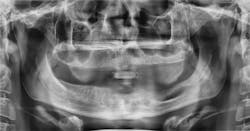

When a radiograph is taken, the dental professional may see what appears to be the outline of the root socket where an extraction has occurred, usually many years prior to any complaints (figures 1 and 2). This is a residual socket or residual root socket. The outline of the tooth’s root cavity is faintly visible, and when examined surgically, it may be hollow or filled with dense fibrous scar tissue, granulation tissue, or very immature bone.

Figure 1: Residual sockets. Note the outline of the previous roots of the molar tooth. Courtesy of Jerry E. Bouquot, DDS, MSD, DABOMP, DABOM (hon), FAAOMP, FICD, FACD, FRCM (UK), emeritus professor and past chair, Department of Diagnostic and Biomedical Sciences, University of Texas, Houston, Texas.